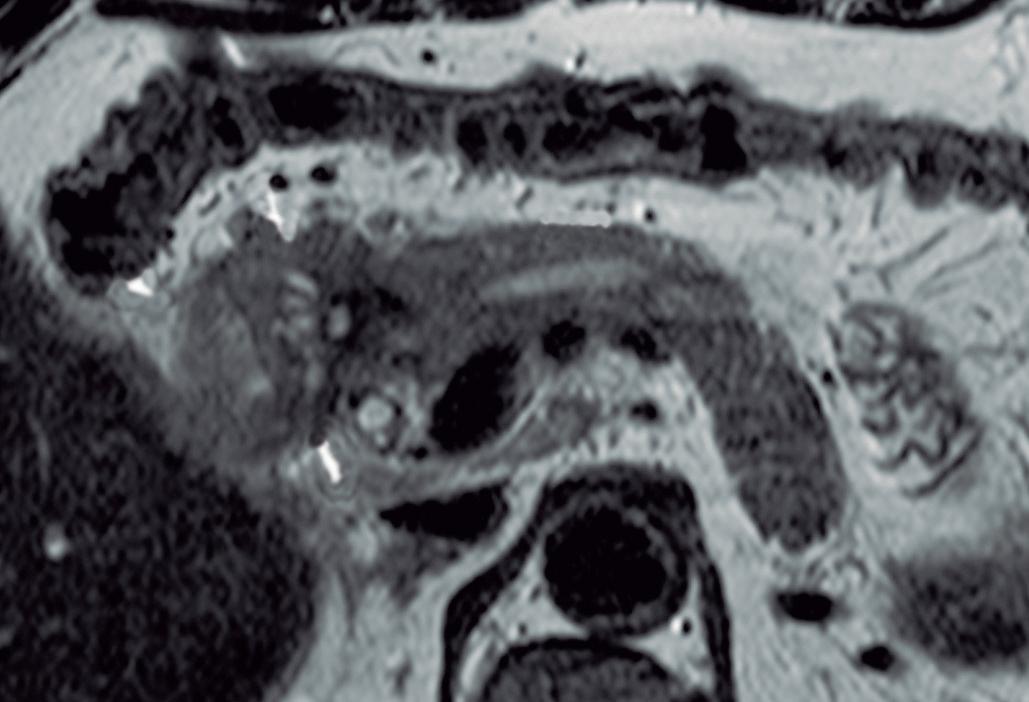

Hipoplasia pancreática

La agenesia pancreática completa es incompatible con la vida y extremadamente infrecuente. La agenesia parcial o hipoplasia puede involucrar el brote ventral o dorsal, con mayor frecuencia este último. Puede ser una condición aislada o bien estar asociada al síndrome de heterotaxia - poliesplenia. En la hipoplasia del páncreas dorsal se observa la porción cefálica y el proceso uncinado de aspecto redondeado, con ausencia del cuello, cuerpo y cola. Suele observarse relativa prominencia

del proceso uncinado, que se prolonga por detrás de los vasos mesentéricos (Figura 15). Es imprescindible efectuar el diagnóstico diferencial y descartar exhaustivamente una lesión neoplásica que provoque atrofia del páncreas corpocaudal, distal al tumor. Los individuos con agenesia del páncreas dorsal suelen ser asintomáticos, aunque se ha descripto un riesgo incrementado de padecer diabetes debido a que el mayor porcentaje de los islotes de células de Langerhans se hallan en el páncreas distal. 27

parcial del brote dorsal)

A) Resonancia magnética, secuencia T2, plano coronal. Se observa un páncreas “truncado”, con ausencia de tejido glandular a la izquierda del cuello (flecha), coincidente con una agenesia parcial del brote embriológico dorsal. La cabeza de flecha nos muestra a la porción cefálica prominente, redondeada. B) Resonancia magnética, secuencia T1 con contraste, plano axial. Flecha: Limite de finalización de la glándula, a la izquierda de la arteria mesentérica superior. Cabeza de flecha: Porción cefálica prominente, redondeada. C) Resonancia magnética, secuencia T1 con contraste, plano axial, corte más caudal. Las flechas muestran hipertrofia relativa del proceso uncinado (brote ventral), el cual llega a ubicarse por detrás de los vasos mesentéricos superiores, incluso superando el plano de la arteria. AMS: arteria mesentérica superior.

Figura 15. Hipoplasia pancreática (Agenesia